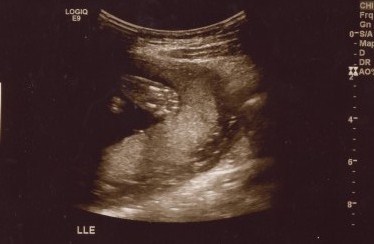

For an hour and a half today we watched, smiled, and cried at the images of our sweet baby boy. I learned a new kind of love today and my heart is full. I can't get enough of his little profile. We are so very blessed. Meet our little guy: